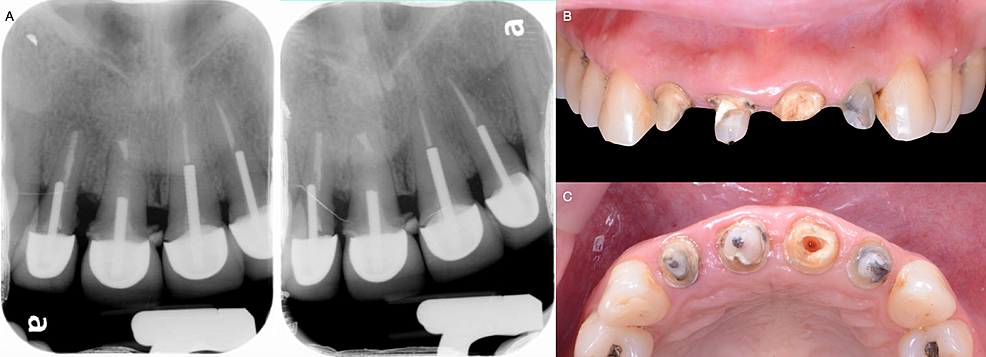

After a detailed clinical evaluation, the maxillary right lateral incisor, central incisor, and maxillary left lateral incisor were diagnosed with mobility grade II. Incisal wear was found on the maxillary right and left canines. Radiographic evaluation showed the old crowns and metal posts on the maxillary left lateral incisor, central incisor, and right lateral incisor (Figure 2A). The patient had high esthetic demands and showed interest in having fixed all-ceramic restorations from the right maxillary canine to the left canine. Fortunately, the patient had a low smile line, and gingival inflammation and disharmony were not showing while smiling. The patient was informed of the need to remove the old crowns to re-assess the teeth’ clinical situation and agreed to the procedure.

The existing restorations of the maxillary incisors were removed, and secondary caries were found in all teeth. A fractured core was observed on the maxillary left central incisor with grade II mobility on all teeth (Figures 2B, 2C). Therefore, these teeth were deemed hopeless. The patient was presented with the option of having two implants placed to support a fixed prosthesis from the maxillary left lateral incisor to maxillary right lateral incisors and single restorations on the maxillary right and left canines. The patient approved the plan, and the treatment was initiated.